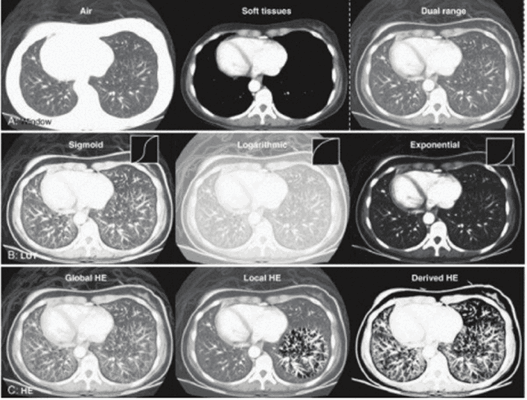

Рис. 9. Иллюстрация применения различных компьютерных методов изменения контрастности томографического изображения.